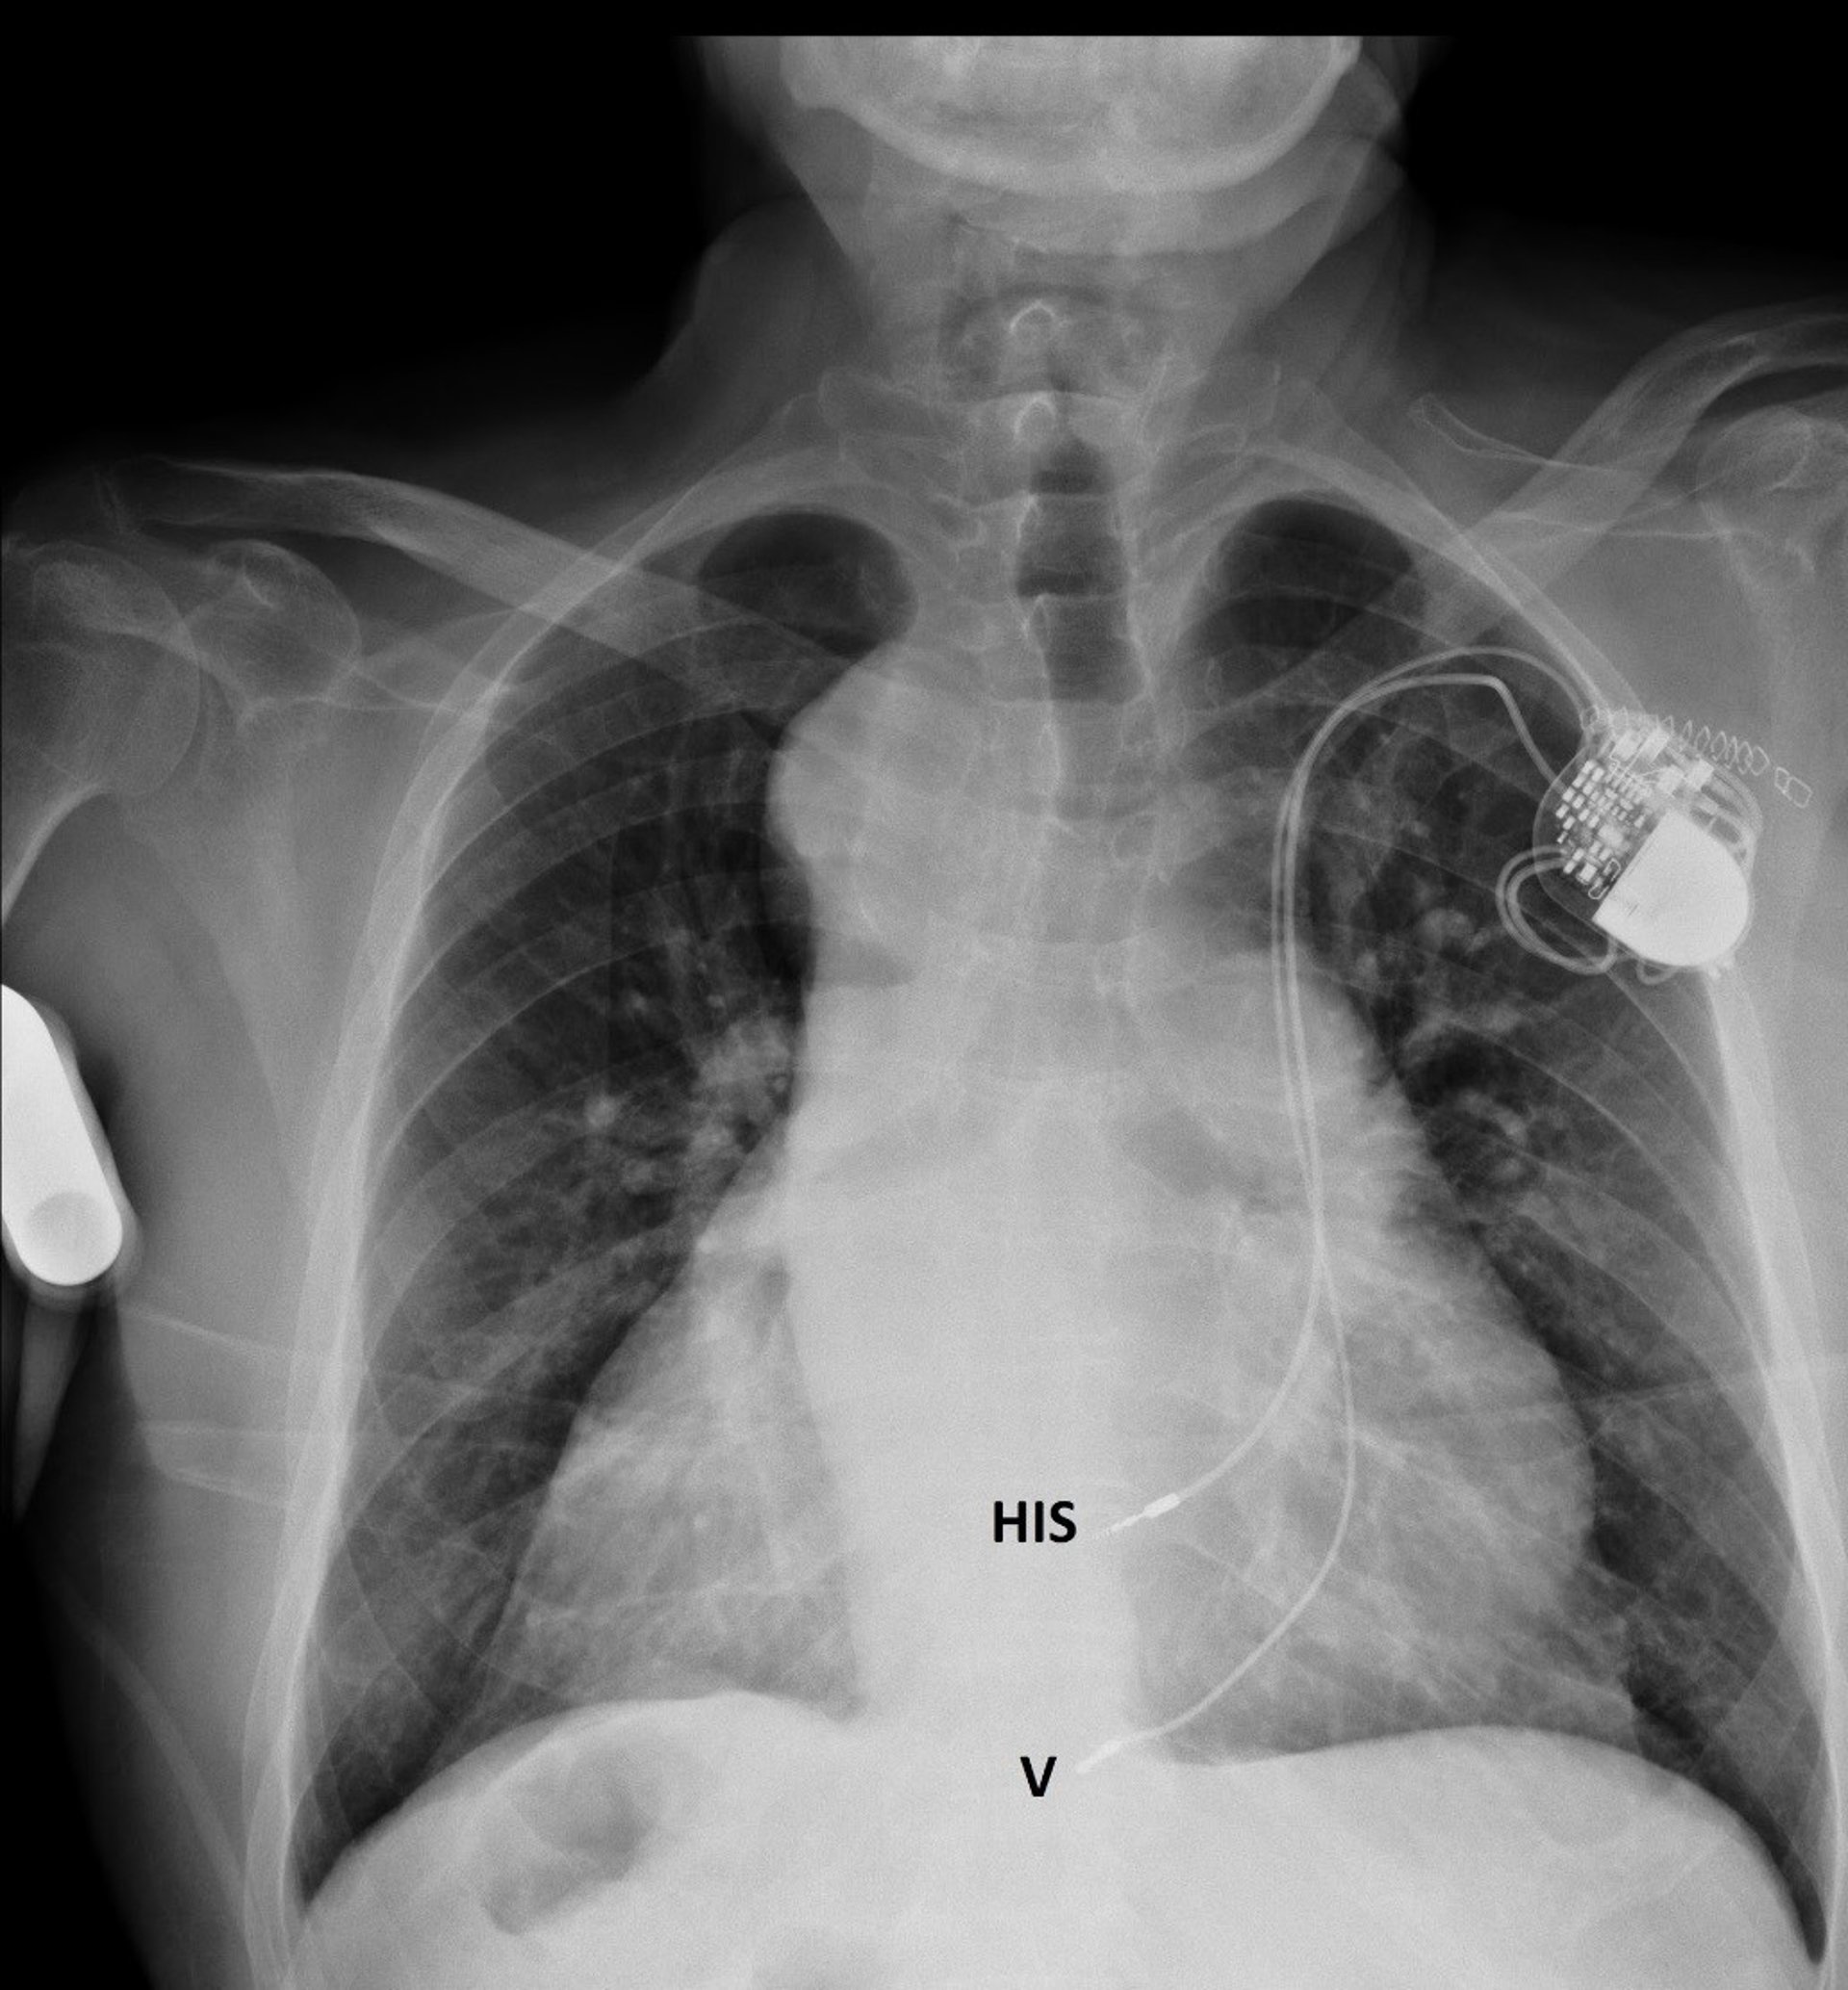

Archivo - Estimulador hisiano

Archivo - Estimulador hisiano - JUNTA DE ANDALUCÍA - Archivo

"Si estimulamos la rama izquierda del haz de Hiss, conseguimos la estimulación buscada, muy parecida a la normal del corazón, muy estable y prácticamente sin fracasos", ha explicado el doctor Jiménez Mena.